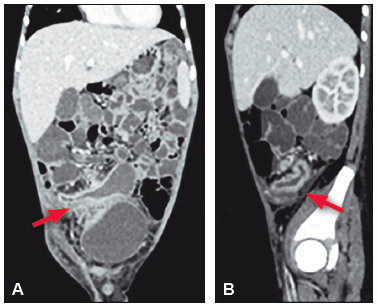

La radiografía de abdomen de pie mostró niveles hidroaéreos a nivel de FID (Figura 1). En la ecografía abdominal se encontró engrosamiento de asas, discreta alteración de la ecoestructura y aumento de la vascularización al Doppler color en FID. Se realizó además una RMN de intestino delgado que evidenció la dilatación de las asas del íleon distal con un área de estenosis cercana a la válvula ileocecal y colección heterogénea para-vesical derecha asociada a un marcado aumento de la ecogenicidad de la grasa mesentérica y múltiples ganglios de 4 x 3,2 cm (Figura 2).

Figura 2. RMN de abdomen con contraste en cortes coronales (A) y sagitales (B) con

evidencia de un área de estenosis cercana a la VIC con dilatación proximal de íleon distal